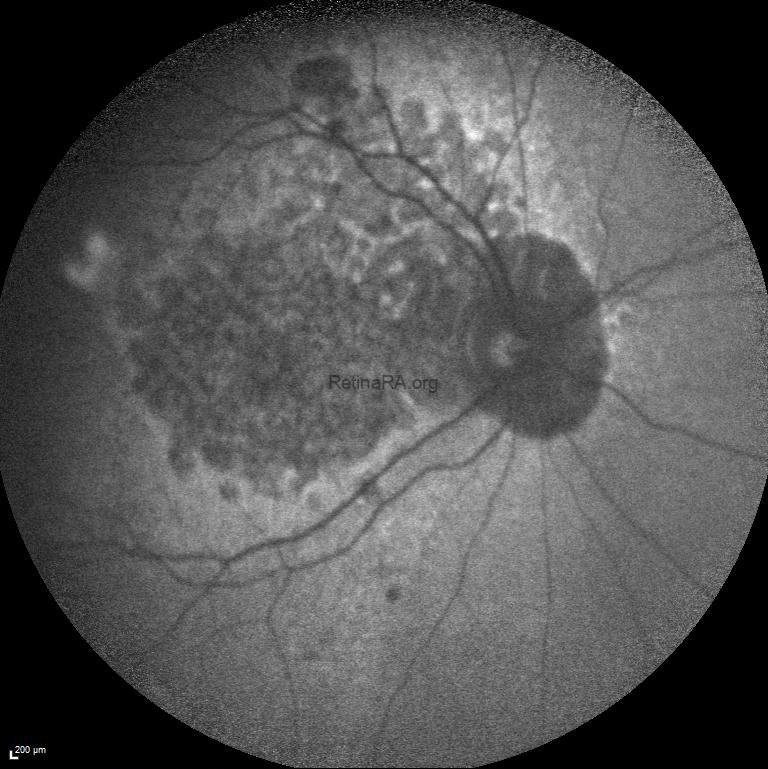

Fundus examination of the right and left eyes revealed subretinal pigment epithelium drusen-like deposits extending from the macula to the mid periphery in both eyes in addition to macular atrophy.

Blue-light macular fundus autofluorescence and wide-field fundus autofluorescence revealed decreased autofluorescence at the macula and increased autofluorescence in mid-peripheral retina.